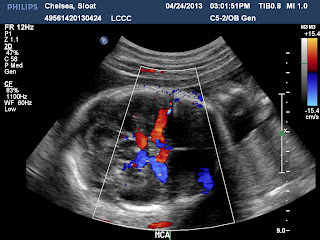

| Both of these are uterine blood flow, both a perfect average of 3.1. Yay! |

Blood flow through the umbilical cord.